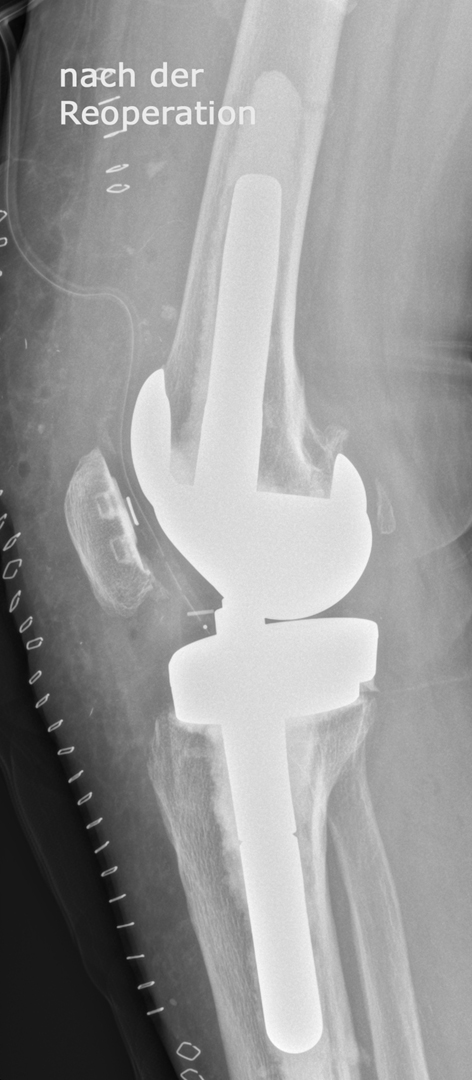

Reoperationen von gelockerten Gelenksprothesen

Reoperationen von gelockerten Gelenksprothesen sind anspruchsvolle operative Eingriffe , bei denen die Erfahrung des Operateurs und die Gabe zur richtigen Einschätzung der optimalen Versorgungsform von grosser Bedeutung ist. Reoperationen können dann erforderlich werden, wenn das Gefüge zwischen Knochen und Prothese aufgelockert wird – so kann eine Entzündung, ein vermehrter Abrieb der Prothesenteile, ein Bruch des die Prothese umgebenden Knochens aber auch Verletzungen der Weichteile eine Prothesenlockerung verursachen. Rasches Handeln ist dann angezeigt wenn der Patient über Schmerzen klagt, Röntgenuntersuchungen die Änderung der Prothesenposition

erkennen lassen oder Spezialuntersuchungen wie zum Beispiel eine Szintigraphie Hinweis auf eine Prothesenlockerung geben. Der operative Eingriff selbst ist für den Patienten belastend aber nur durch rasches Handeln kann die weitere Zerstörung von Knochen und Weichteilen verhindert werden.